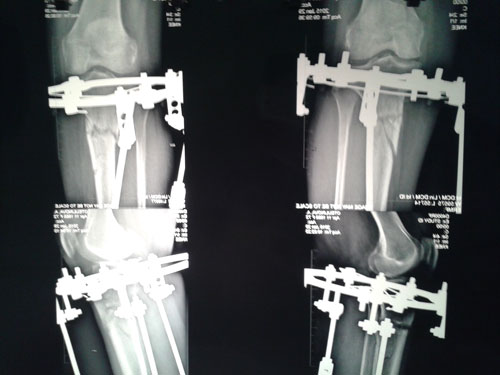

рентген в 90 дней.

Костная мозоль растёт хорошо, планируем снятие аппаратов в 4 месяца.

Дата операции 03.12.2014г.

Дата снятия аппаратов 06. 04.2015г.

Срок лечения 4 месяца.